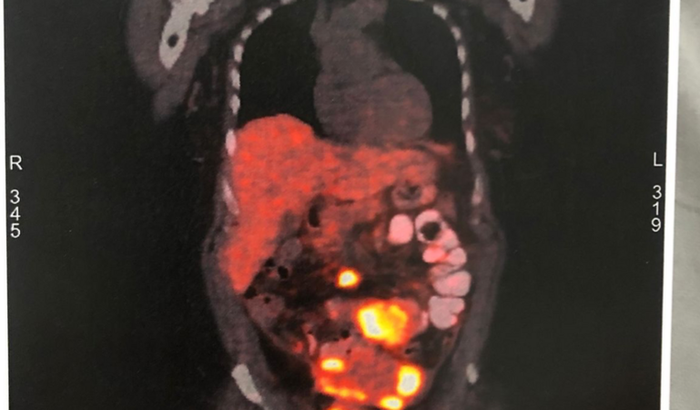

Olá gente! Criei essa vaquinha on-line para ajudar no tratamento do câncer da minha mãe! Vou contar um pouco da história para vocês: minha mãe (Shirley Alencar Correia de Oliveira) teve câncer de intestino em 2013. Naquela época, foi necessário fazer uma cirurgia de emergência, a qual retirou cerca de 3.5kg do seu intestino. Segundo os médicos da época, não seria necessário realizar químio ou radioterapia, uma vez que o câncer teria “saído”. Após isso, minha mãe continuou a ter uma vida normal, porém, passou por duas cirurgias de hérnia, e, após a última delas (2021), fizemos alguns exames e descobrimos que o câncer tinha retornado e que estava em estado de metástase. Realizamos diversos exames (muito caros, inclusive), e constatamos que de fato o câncer tinha se espalhado. No último mês de agosto, minha mãe realizou uma cirurgia de emergência, com o objetivo de desobstruir o intestino, mas o cirurgião nos disse que a única alternativa no momento é a utilização de uma medicação específica para o seu caso, que custa em média R$5.000,00, por mês. De acordo com o clínico oncológico, essa medicação é para o resto da vida, pois, primeiro devemos estabilizar a doença, para depois tentarmos uma nova intervenção cirúrgica. Assim, gostaria de pedir ajuda a vocês para que nós possamos custear esse tratamento caríssimo! Aqueles que não puderem ajudar com valores, podem ajudar compartilhando e orando por nós! Muito obrigada a todos, com fé em Deus venceremos!